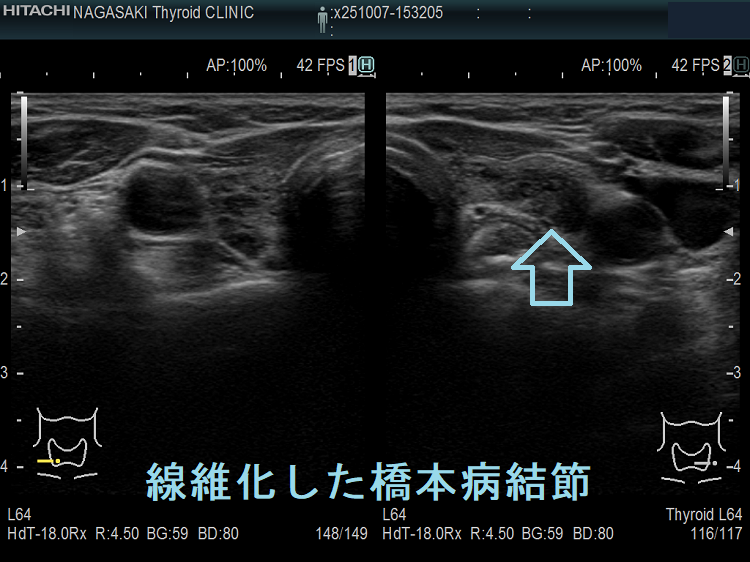

橋本病(慢性甲状腺炎)ではリンパ球浸潤に伴う炎症から濾胞細胞の好酸性変性[好酸性細胞(Hürthle細胞,ハーテル細胞)]・過形成、浮腫、線維化で結節性病変を形成[結節性橋本病(橋本病結節)]。病理学的に腺腫様甲状腺腫・腺腫様結節と同じで、橋本病(慢性甲状腺炎)を基盤とする腺腫様甲状腺腫・腺腫様結節。超音波(エコー)検査では内部が極めて低エコーのため甲状腺癌、甲状腺原発悪性リンパ腫と鑑別必要。細胞診では好酸性細胞、リンパ球集簇、炎症性多核巨細胞を認め、甲状腺乳頭癌ワルチン腫瘍型、通常型甲状腺乳頭癌・亜急性甲状腺炎と鑑別要。

橋本病(慢性甲状腺炎)では、リンパ球浸潤に伴う炎症から、濾胞細胞の好酸性変性・過形成、浮腫、線維化などの変化で結節性病変が形成されます[結節性橋本病(橋本病結節)]。病理学的には腺腫様甲状腺腫・腺腫様結節と同じ事で、橋本病(慢性甲状腺炎)を基盤とする腺腫様甲状腺腫・腺腫様結節になります。

橋本病リンパ球浸潤、橋本病結節 どちらともとれる見え方です。境界がはっきりしているので橋本病結節とも言えるし、炎症性変化が主体なので橋本病リンパ球浸潤とも言えます。